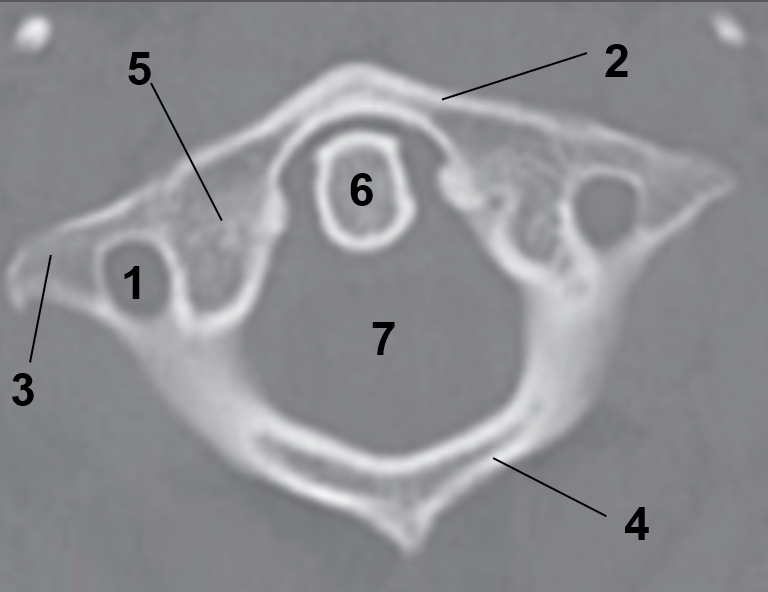

1?

Hard Palate

2?

Maxillary Bone

3?

Mandibular Rami

4?

Dens

5?

Transverse Foramen C1

6?

Spinal Cord

7?

Auricle

8?

Atlas